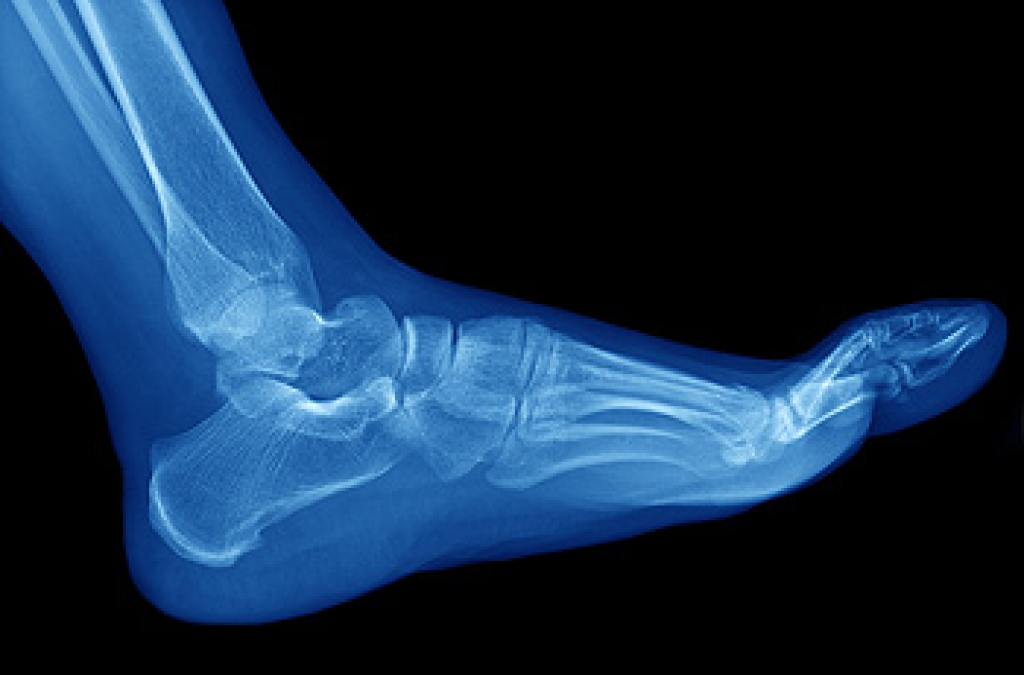

Stress fractures can be common among athletes. They can happen as a result of the consistent pressure that the bones of the feet endure during the athlete’s chosen sport. Stress fractures are defined as small, hairline fractures in the bones which may make walking and running difficult. Common symptoms can include pain surrounding the affected bone, which may improve when the foot is resting and elevated. Some patients experience bruising and swelling, accompanied by achiness. Additionally, stress fractures may gradually develop as a result of wearing shoes that do not fit properly, and this may weaken the foot bones. If you have pain in your foot, it is suggested that you consult with a podiatrist who can diagnose and treat stress fractures.

Stress fractures are the result of repetitive force being placed on the bone. Since the lower leg and feet often carry most of the body’s weight, stress fractures are likely to occur in these areas. If you rush into a new exercise, you are more likely to develop a stress fracture since you are starting too much, too soon. Pain resulting from stress fractures may go unnoticed at first, however it may start to worsen over time.